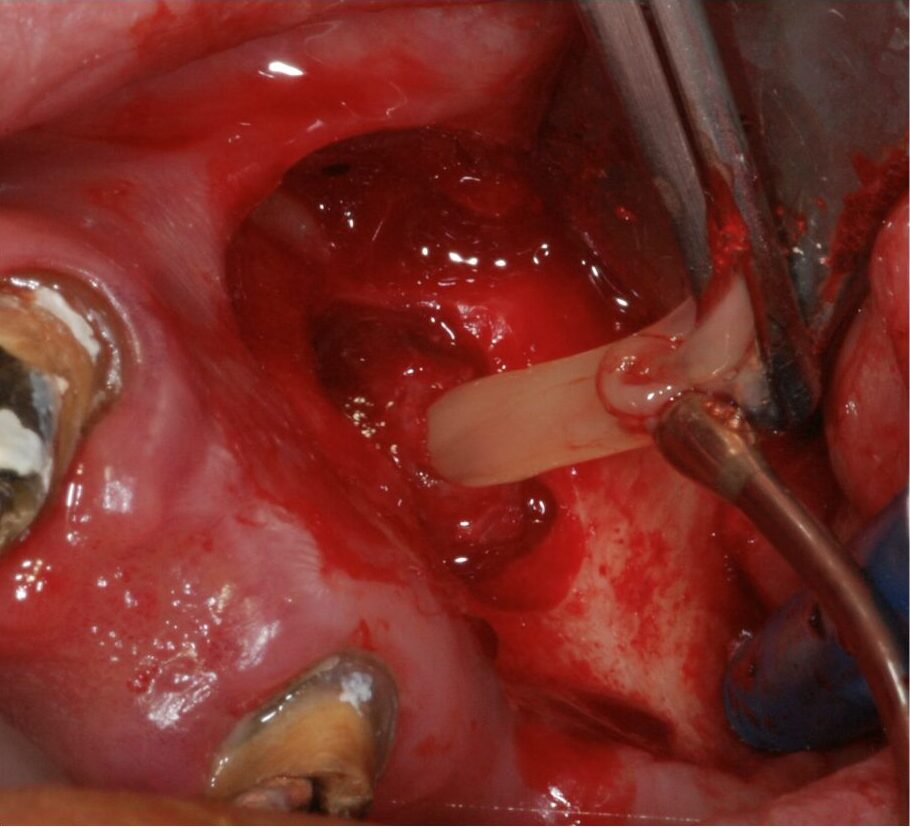

• INTERVENTI DEI CORSISTI SU PAZIENTI

• DISCUSSIONE DEI CASI OPERATI DAI CORSISTI